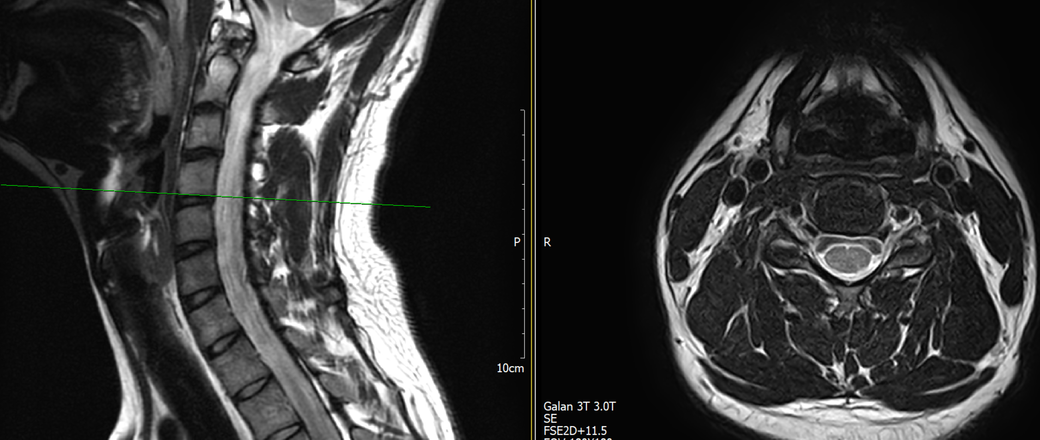

목과 오른쪽 어께 통증이 있어 mri를 찍어왔는데, 사진에서 의심되는 부분 있을까요?

통증은 10년 정도 되었고, 통증 의학과 가서 신경차단술 2회 받은 상태입니다.

토요일에 mri 찍고 주말이라 물어볼 곳이 없어 먼저 여기에 사진 올려봅니다. 답변 부탁드립니다.

MRI만 보면 굉장히 깨끗한 목입니다.

디스크탈출은 없고 신경뿌리가 압박될만한 모습도 전혀 보이지 않습니다.

통증 의학과에서는 아마 MRI 없이 증상을 기반으로 신경차단술을 하셨을거라 생각됩니다.

지금은 MRI에서 잘 보이지 않는 디스크내장증일 가능성이 높아보이며 경추전만 자세를 잘 유지해주시는게 가장 큰 도움이 되겟습니다.